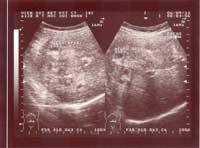

Một số hình ảnh siêu âm tổn thương gan do sán lá gan lớn:

Hình ảnh 3: Nhiều khối tổn thương gan do SLGL điển hình: 3 khối tổn thương | Hình ảnh 4: Nhiều khối tổn thương gan do SLGL điển hình: 2 khối tổn thương |